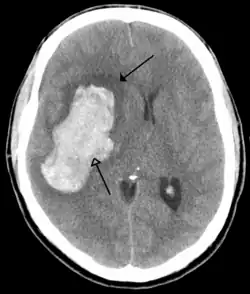

Most strokes result from loss of blood supply, typically because of an embolus, rupture of a fatty plaque causing thrombus, or narrowing of small arteries. Strokes can also result from bleeding within the brain.[193] Transient ischaemic attacks (TIAs) are strokes in which symptoms resolve within 24 hours.[193] Investigation into the stroke will involve a medical examination (including a neurological examination) and the taking of a medical history, focusing on the duration of the symptoms and risk factors (including high blood pressure, atrial fibrillation, and smoking).[194] Further investigation is needed in younger patients.[195] An ECG and biotelemetry may be conducted to identify atrial fibrillation; an ultrasound can investigate narrowing of the carotid arteries; an echocardiogram can be used to look for clots within the heart, diseases of the heart valves or the presence of a patent foramen ovale.[195] Blood tests are routinely done as part of the workup including diabetes tests and a lipid profile.[195]

Some treatments for stroke are time-critical. These include clot dissolution or surgical removal of a clot for ischaemic strokes, and decompression for haemorrhagic strokes.[196][197] As stroke is time critical,[198] hospitals and even pre-hospital care of stroke involves expedited investigations – usually a CT scan to investigate for a haemorrhagic stroke and a CT or MR angiogram to evaluate arteries that supply the brain.[195] MRI scans, not as widely available, may be able to demonstrate the affected area of the brain more accurately, particularly with ischaemic stroke.[195]